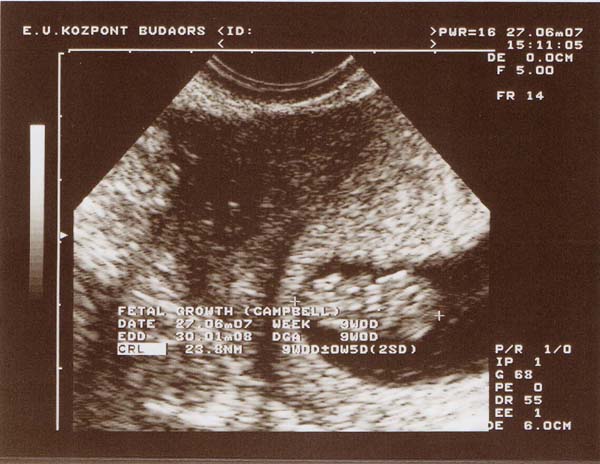

Hatalmas gratula! Nagyon szép kiscsaj! szépen látszik a pofija, s az öt ujja is